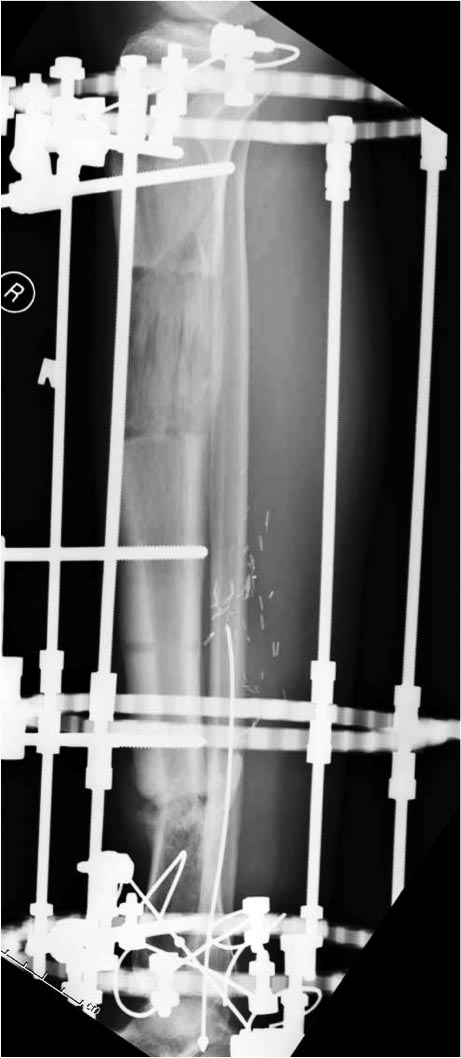

Данный случай не огнестрельная рана, а результат мотоциклетной аварии.

Независимо от повреждения при таких обширных дефектах мягких и костной

тканей применяется схожая тактика. Как видно, после нескольких I&D для

создания “pseudo membrane” применили цилиндрический блок из цемента.

Дефект мягких тканей закрыли свободным Anterior Thigh Graft. Из малого

доступа цилиндр удален небольшими кусочками, а пространство заполнили

бусами для освобождения пространства. По мере приближения регенерата

освободили пространство удалением бус через небольшой разрез. Этап

созревание регенерата можно было ускорить усилением интрамедуллярным

гвоздем, но решили закончить методом Илизарова.